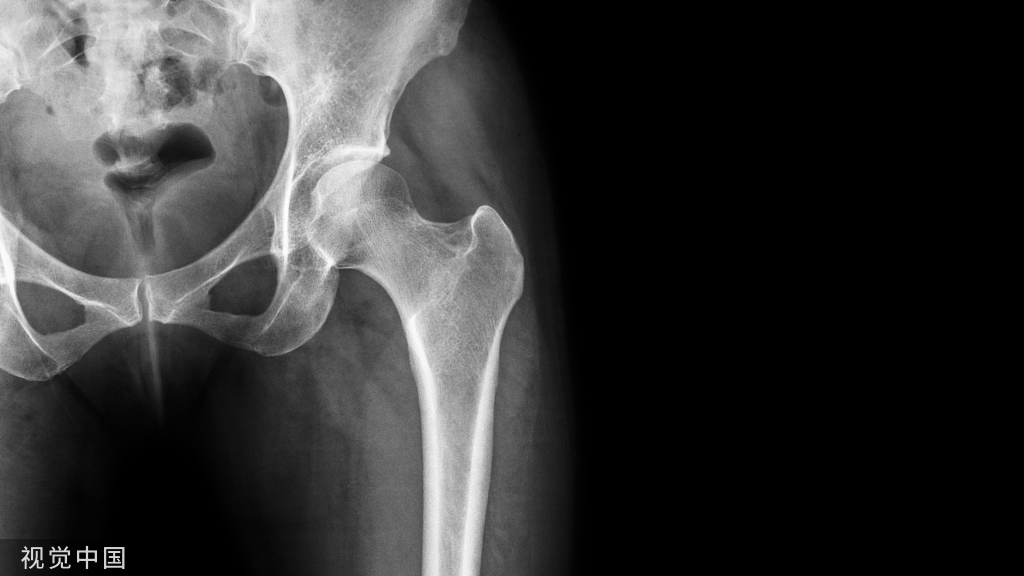

医生还会检查患者的头部、颈部、脸部和下巴是否有压痛,关节是否发出弹响或者摩擦声,或者是否有运动困难。医生也可能建议进行影像学检查,如X光、磁共振成像(MRI)或 CBCT。

↑颞下颌关节↑